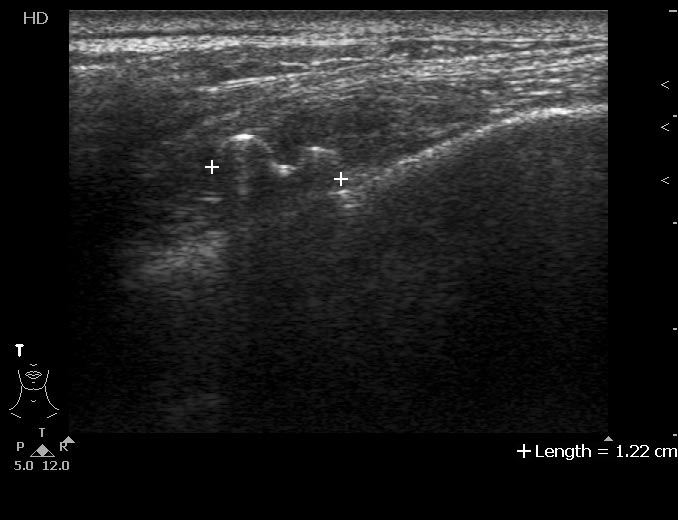

Сонограммы

Впервые встречаю подобное. Ваше мнение?

На снимке утолщение веретенообразное мышечного слоя с наличием кальцификатов(два) Кальцификаты в мышце чаще встречаются при паразитарных инфекциях(трихиниллез,токсоплазмоз,цистецеркоз),но их больше по количеству и в разных местах.Оссифицирующий миозит-имеет свою картину и распространение.Насчет Хортона-навряд ли,это же поражение сосуда.Насчет тофусов-они содержат ураты,чаще локализуются подкожно(не в мышце),при подагре осификации вдоль сухожилий.А может был удар,гематома с частичной кальцификацией?

Если в анамнезе подагра, то тогда я за скопление солей уратов. Эта гадость может накапливаться где угодно, я сам видел и смотрел публикации коллег, когда это тофусы и в брюшной полости находили, а уж в мягких тканях, так это и подавно. Тем более что это болит, кальцинированная гематома не болела бы.